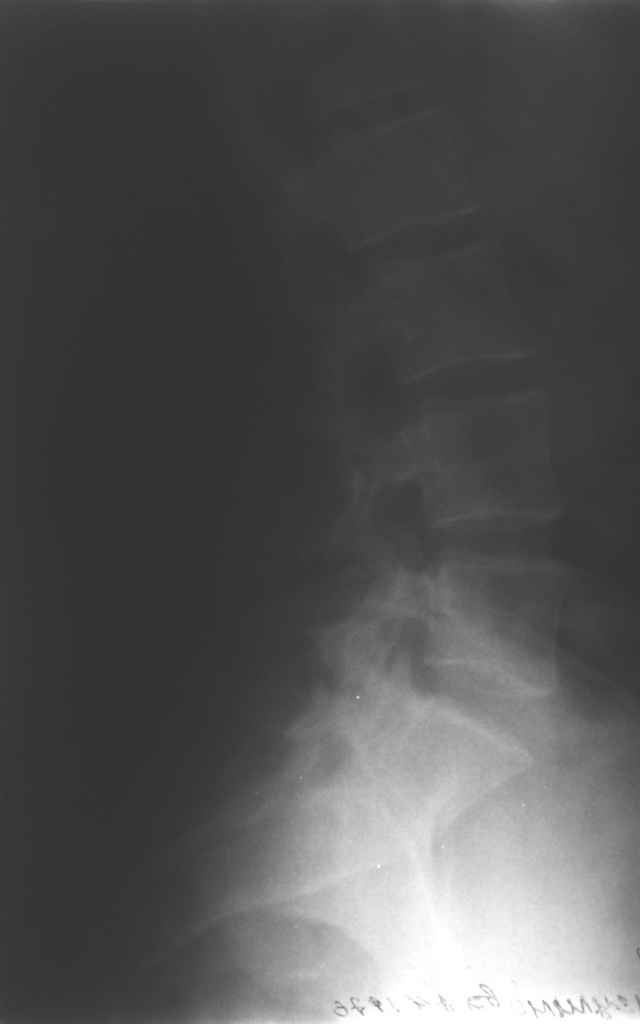

13/03/03 |  13/03/03 |  13/03/03 |  15/09/06 |  15/09/06 |  07/03/07 |  07/03/07 |  19/12/06 | К нам в клинику поступила пациентка 30 лет с диагнозом: Постравматическая ротационная стабильная деформация тазового кольца. Относительное укорочение левой н\конечности на 1 см. Левосторонний компенсаторный сколиоз 2 ст. Болевой синдром. травма автодорожная в январе 2003г. Пассажирка переднего сидения ваз 2109. лечились положением по Волковичу. С марта 2003 года жалуется на боли в тазу, ппояснице усиливающиеся при движении.В настоящее время жалобы на боли в области крестца, КПС больше слева, в пояснично-крестцовом отделе позвоночника. неприятные ощущения, щелчок при выпрямлении правого тазобедренного сустава из положения полного сгибания. боли в тазу появляются при ходьбе ч\з 100 м, так же при вставании из положения сидя, после сидения в течении 2-3 часов. при ходьбе более 100 м появпяется зябкость стоп больше справа. ходит при помощи трости в правой или в левой руке. без трости боли появляются сразу после начала ходьбы. пальпация болезненна в паравертебральных точках средне-грудного и пояснично-крестцового отделов позвоночника, КПС с обеих сторон. Объем движений в тазобедренных суставах полный.правый КПС заблокирован. симптомы натяжения с обеих сторон отрицательны.С 2003г. лечится консервативно, получала ЛФК, массаж, физиолечение - без эффекта. в 2005г. лечилась в санатории с ортопедическим уклоном, получала плавание в минеральной воде, магнитотерапия, массаж, ЛФК. отмечала умеренное улучшение в течении 2 недель.Вопросы:надо ли оперировать, т.е. устранять относительное укорочение левой н\конечности и как?Если не оперировать, то как лечить консервативно?Р-граммы, КТ прилогаются.

Проблема Вашей пациентки находится на границе интересов специальностей ортопедия (вертебралогия) и неврология (нейрохирургия), вероятно, поэтому так мало откликов на ваше обращение. Представленные рентгенограммы не все информативны (особенно спондилограммы от сентября 2006 года). Вероятно, необходимы дополнительные методы исследования к.т. МТГ, ЯМРТ, миелография.

Уважаемый Алексей. Описанные Вами клинические проявления указывают на нестабильность левого крестцово-подвздошного сочленения. Такие больные встречаются не редко (за последние 6мес.в нашей клинике оперировано 3 больных со сроками давности от 6мес. до 1 года). К сожалению рентгенологически их трудно обьективизировать. На КТ это проявляется артрозом и костными разрастаниями КПС. В Вашем случае рентгенограммы и представленные томограммы ничего не дали. Можно попробовать посмотреть связочный аппарат КПС на МРТ хотя не уверен что Вы получите окончательный ответ. Если Вы будете убеждены в этом диагнозе то выход один костно-пластический артродез левого крестцово-подвздошного сочленения с фиксацией канюлированными шурупами. Заманчиво конечно и устранить ротационное смещение половины таза, но это на Ваше усмотрение.

почему она должна возникнуть? Сломан вроде крестец, хотелось бы посмотреть функциональные снимки таза.

Уважаемый Максим. Снимки от 7.03.07 и есть функциональные, т.е. стоя на правой, и левой ноге.